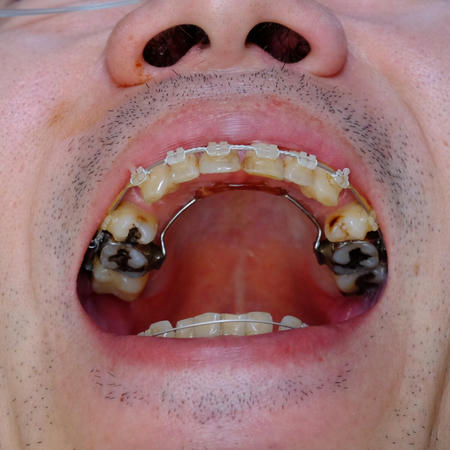

犬歯の移動の様子

これが、2017年12月の、犬歯移動開始直後のもの

これが、2018年8月=今です。移動したとはいえ、3‐4ミリ程度。遅いです。

これが2017年12月の前歯、

18年8月、今です。下顎の前歯がかなり並んだのがわかります。

同じく、2017年12月

2018年8月=今